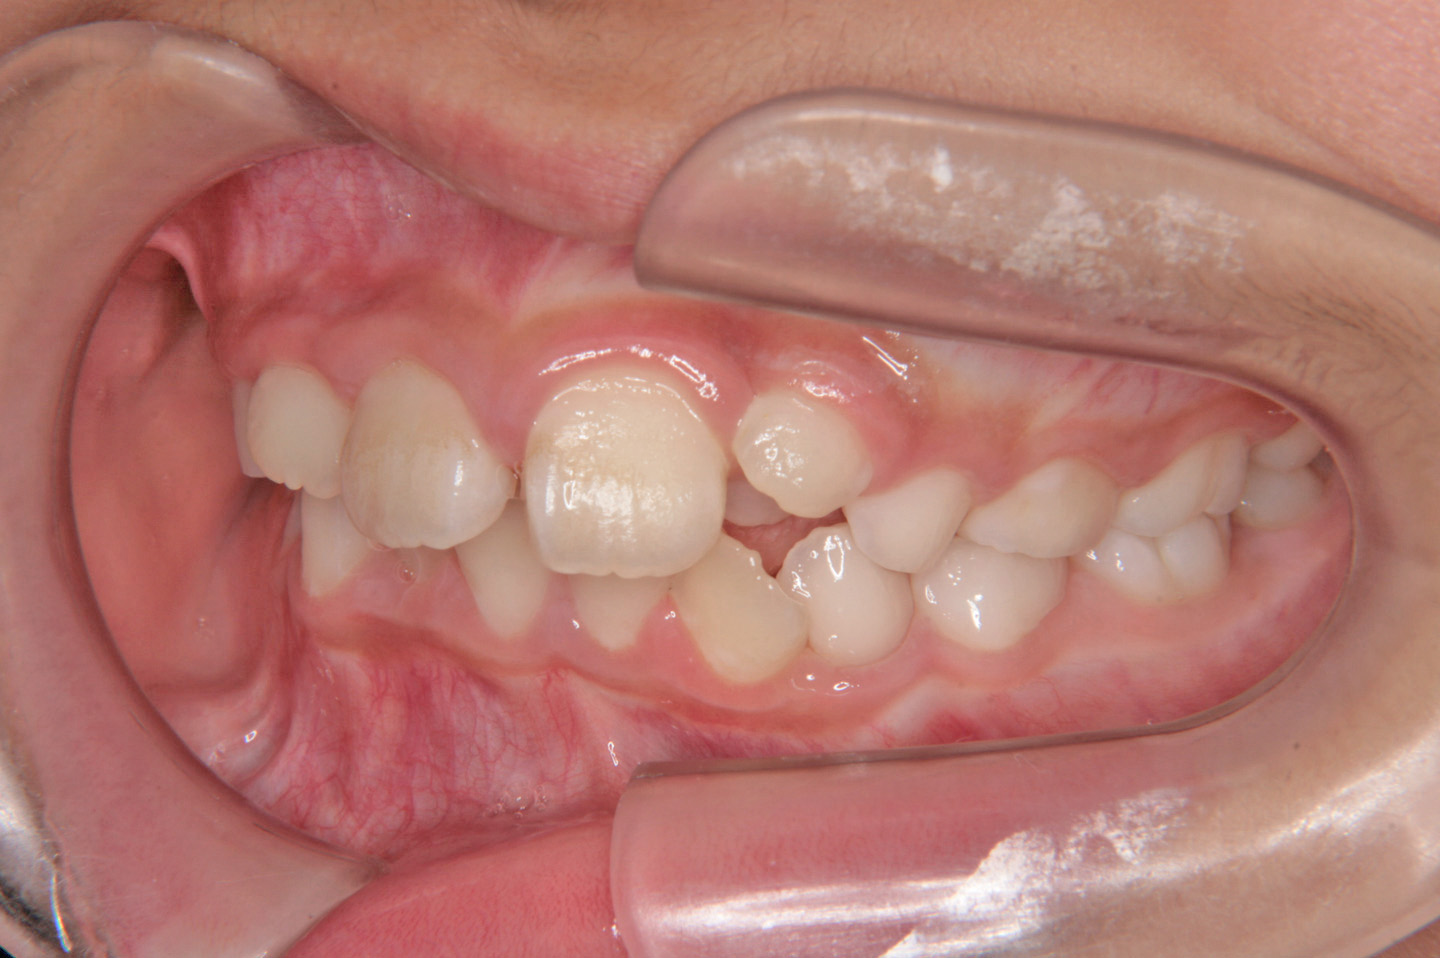

上顎前突(出っ歯)

叢生(乱ぐい歯)

過蓋咬合(深いかみ合わせ)

前歯のデコボコを気にされて来院された7歳の女子です。検査の結果、上顎前突で上下顎ともに歯の並ぶスペースが足りない状態でした。そこで前期治療ではヘッドギアーと拡大床、バイヘリックスを使用し、上顎の成長抑制をしながら、上下顎のスペースを獲得しました。その後、後期治療では非抜歯でエッジワイズ装置を用いて配列を行いました。